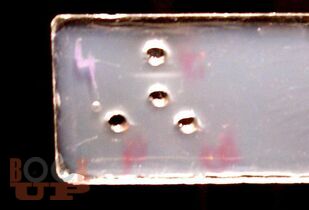

В монографии представлены новые данные об исследовании мочи и желудочного содержимого. Впервые разработаны способы диагностики половой принадлежности мочи по различиям в содержании ядросодержащих и безъядерных клеток и достоверного установления наличия желудочного содержимого на вещественных доказательствах и во внешней среде. В работе приведены результаты исследований о влиянии различных факторов на клеточный состав мочи и на выявляемость желудочного содержимого.